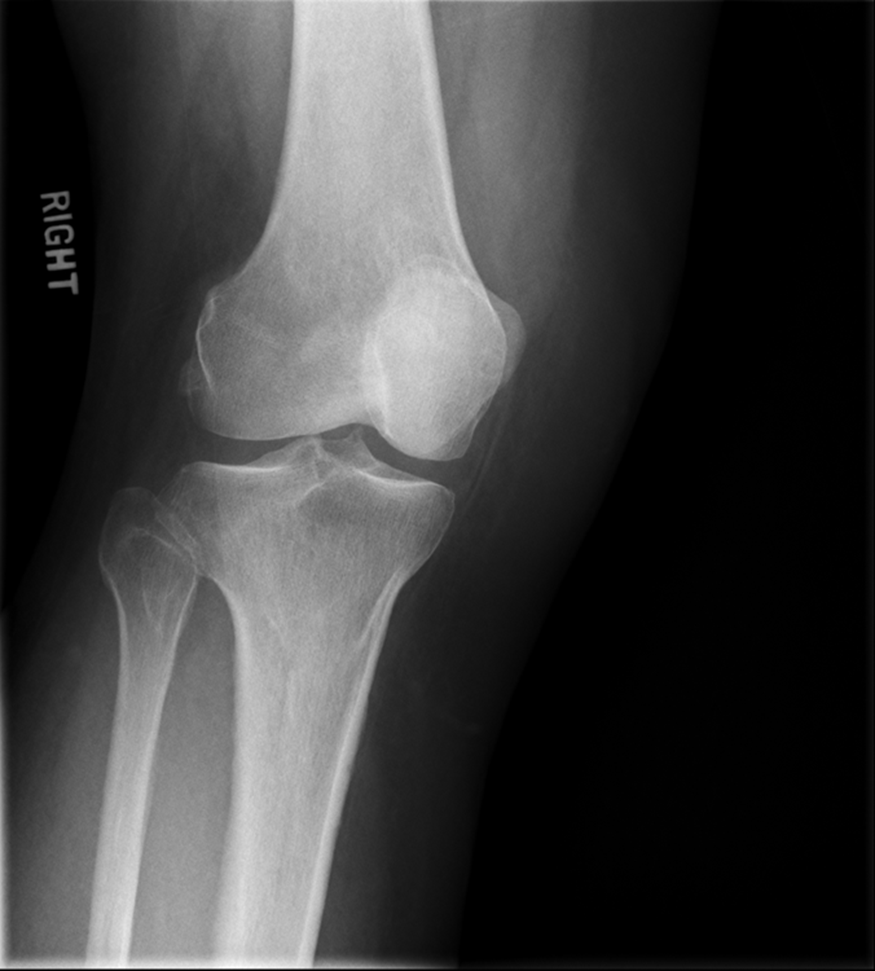

Trauma and Non Trauma AP Knee

•Evidence of proper collimation and the presence of a side marker placed clear of the anatomy of interest

•Knee fully extended if patient’s condition permits

•Entire knee without rotation

•Femoral condyles symmetric and tibia intercondylar eminence centered

•Slight superimposition of the fibular head if the tibia is normal

•Patella completely superimposed on the femur

•Open femorotibial joint space, with interspaces of equal width on both sides if the knee is normal

•Bony trabecular detail and surrounding soft tissues

Lateral Rotation, the fibular head is under the tibia, if patella is towards lateral side usually means it is laterally rotated.

Joint space is not open enough

The width of the joint space is not equal

REPEAT FOR LATERAL ROTATION

Not enough superimposition of the fibular head

Patella is in the center! good! equal distance of joint space/platoes which is good

ACCEPTABLE BECAUSE EVERYTHING ELSE IS GOOD! PATIENT COULD HAVE A MORE SEPARATED FIBULAR HEAD! THEIR ANATOMY IS DIFFERENT. CENTERING IS GOOD